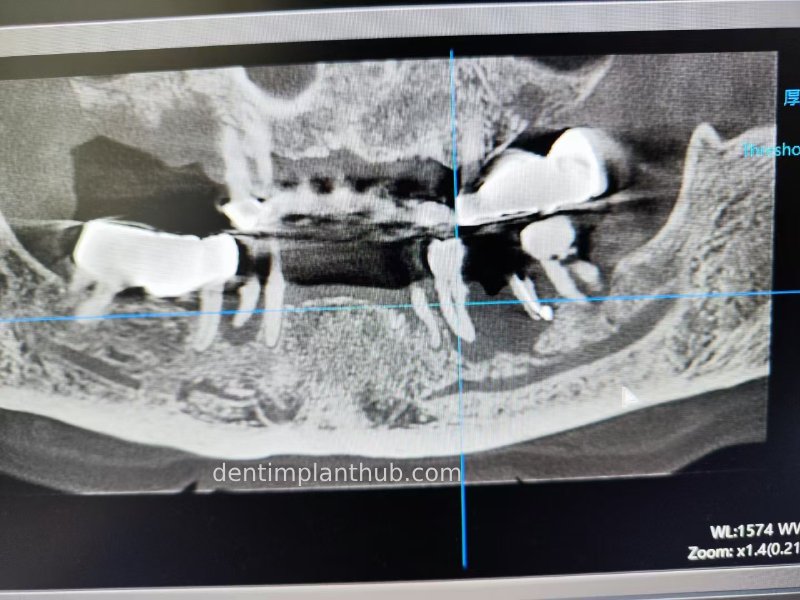

A review of the CBCT on 6/10/23 was more promising and a surgical plan was subsequently drawn up.

46

44

42

32

34

36

General schematic of the surgical programme

Detailed list of implant types and composite abutments to be prepared.

46 tooth position, implant model number 4810, RC series straight composite abutment;

44 tooth position, implant model number 4110, RC series straight composite abutment;

42 tooth position, implant model number 4110, RC series straight composite abutment; alternate implant model number 3310, alternate NC series straight composite abutment;

32 tooth position, implant model number 4110, RC series straight composite abutment; alternate implant model number 3310,. Alternate NC Series Straight Composite Abutment;

34 Dental Position, Implant Model No. 4110, RC Series Straight Composite Abutment;

36 Dental Position, Implant Model No. 4808, RC Series Straight Composite Abutment;